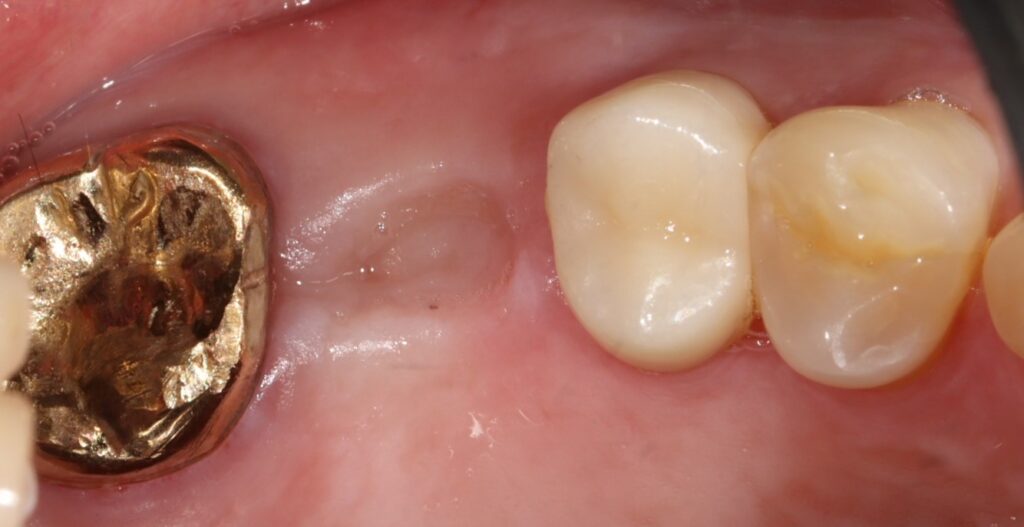

환자분께서는 발치를 하더라도

주변 뼈가 발달되어 있으셔서

치유가 좋을 것으로 예상하고

발치 3개월 후 임플란트 식립을

진행하도록 하였습니다.